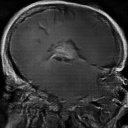

The team and I applied Generative Adversarial Networks (GANs) to address the issues of data scarcity and class imbalance by exploring the use of synthetic data’s ability to augment and replace small datasets. We were able to produce GANs that closely approximated the distribution of the dataset, and determine the optimal parameters and best loss function.

- Trained and tested models, generated synthetic images for reports